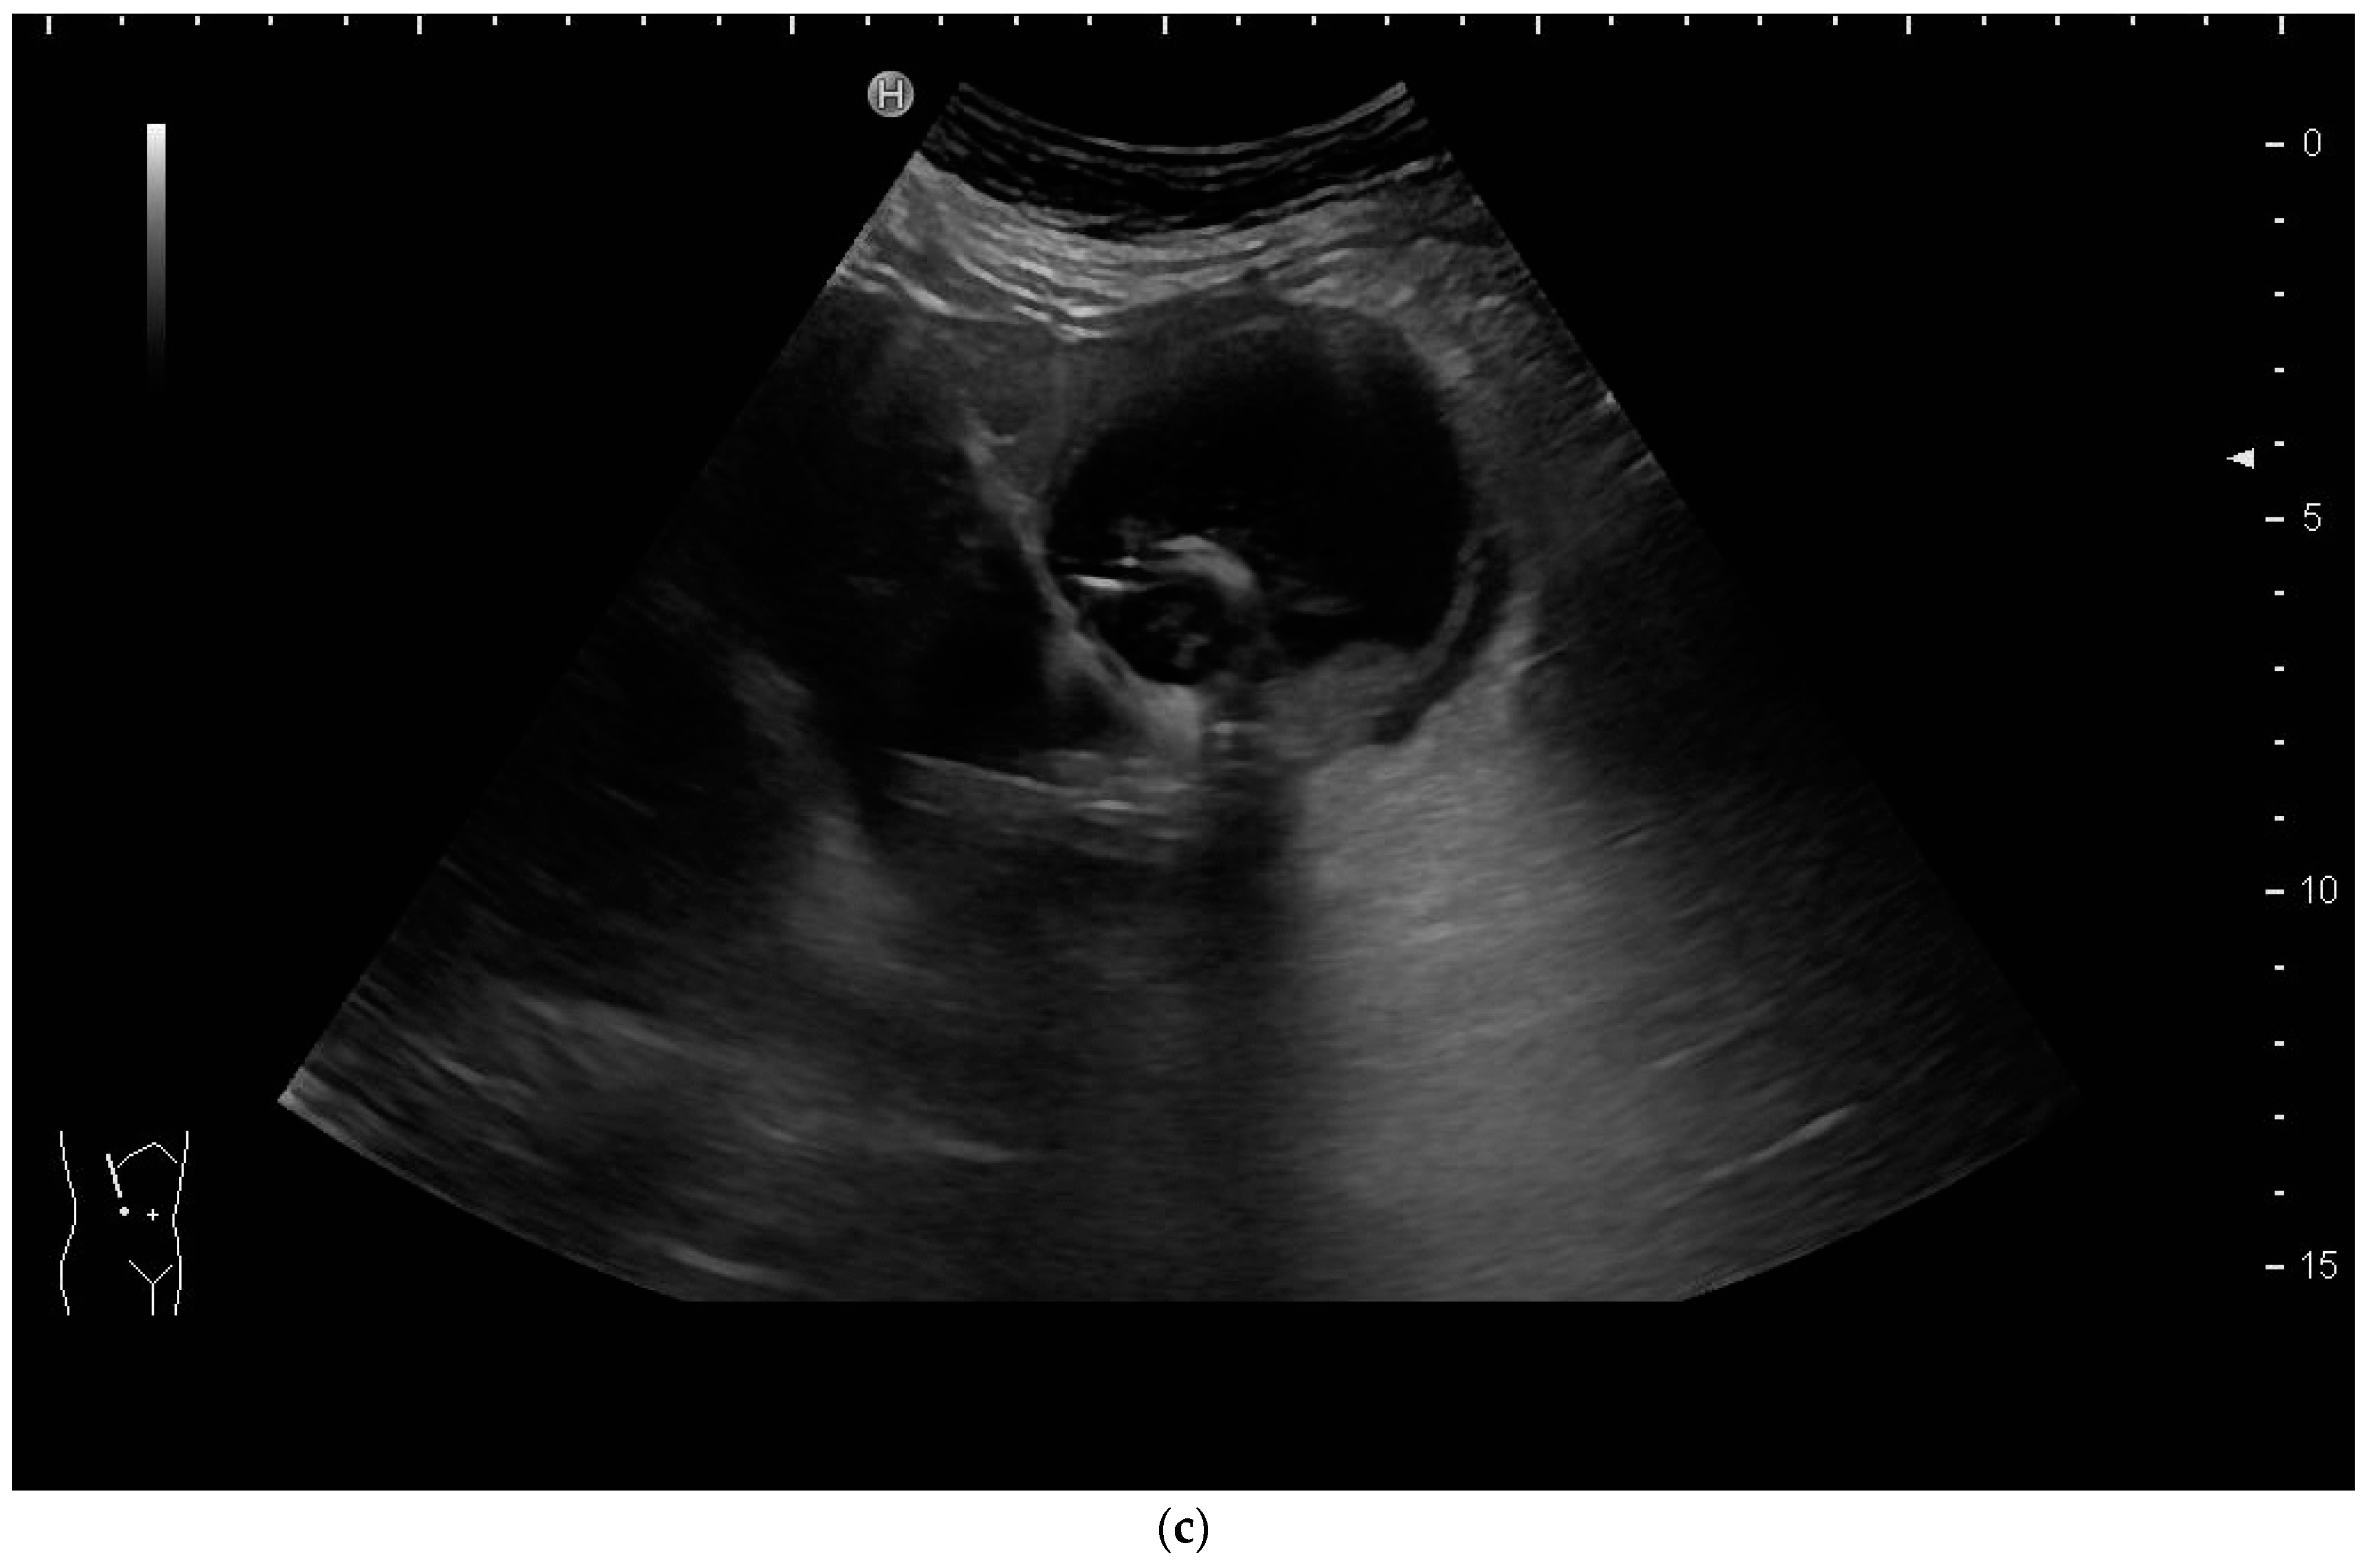

Again, the “in plane” approach is recommended to depict the needle in real time and continuously on its way. This is mandatory because iatrogenic perforation of the posterior gallbladder wall must be avoided. Both the drainage techniques, Seldinger (Figure 11a–c) and trocar (direct puncture, cf. Figure 10), may be used, depending on the physician’s preferences [43,58].

Figure 11.

When using the Seldinger technique, first a Chiba needle is placed in the gallbladder (a), through which a 0.035” guide wire with bended tip is inserted (b). Plastic pigtail drainage (c) is then advanced over the guide wire.

We recommend the use of 8F or 10F pigtail drainage. If it is inserted using Seldinger’s technique, dilatation is not necessary. If the guide wire is confirmed to be in the correct place and is secured well, drainage placement can be performed without US visualisation [43,76].

As tube displacement is a relevant problem, we recommend the use of thread-locked catheters, which are supposed to keep the pigtail in its curled shape, thereby preventing dislocation.